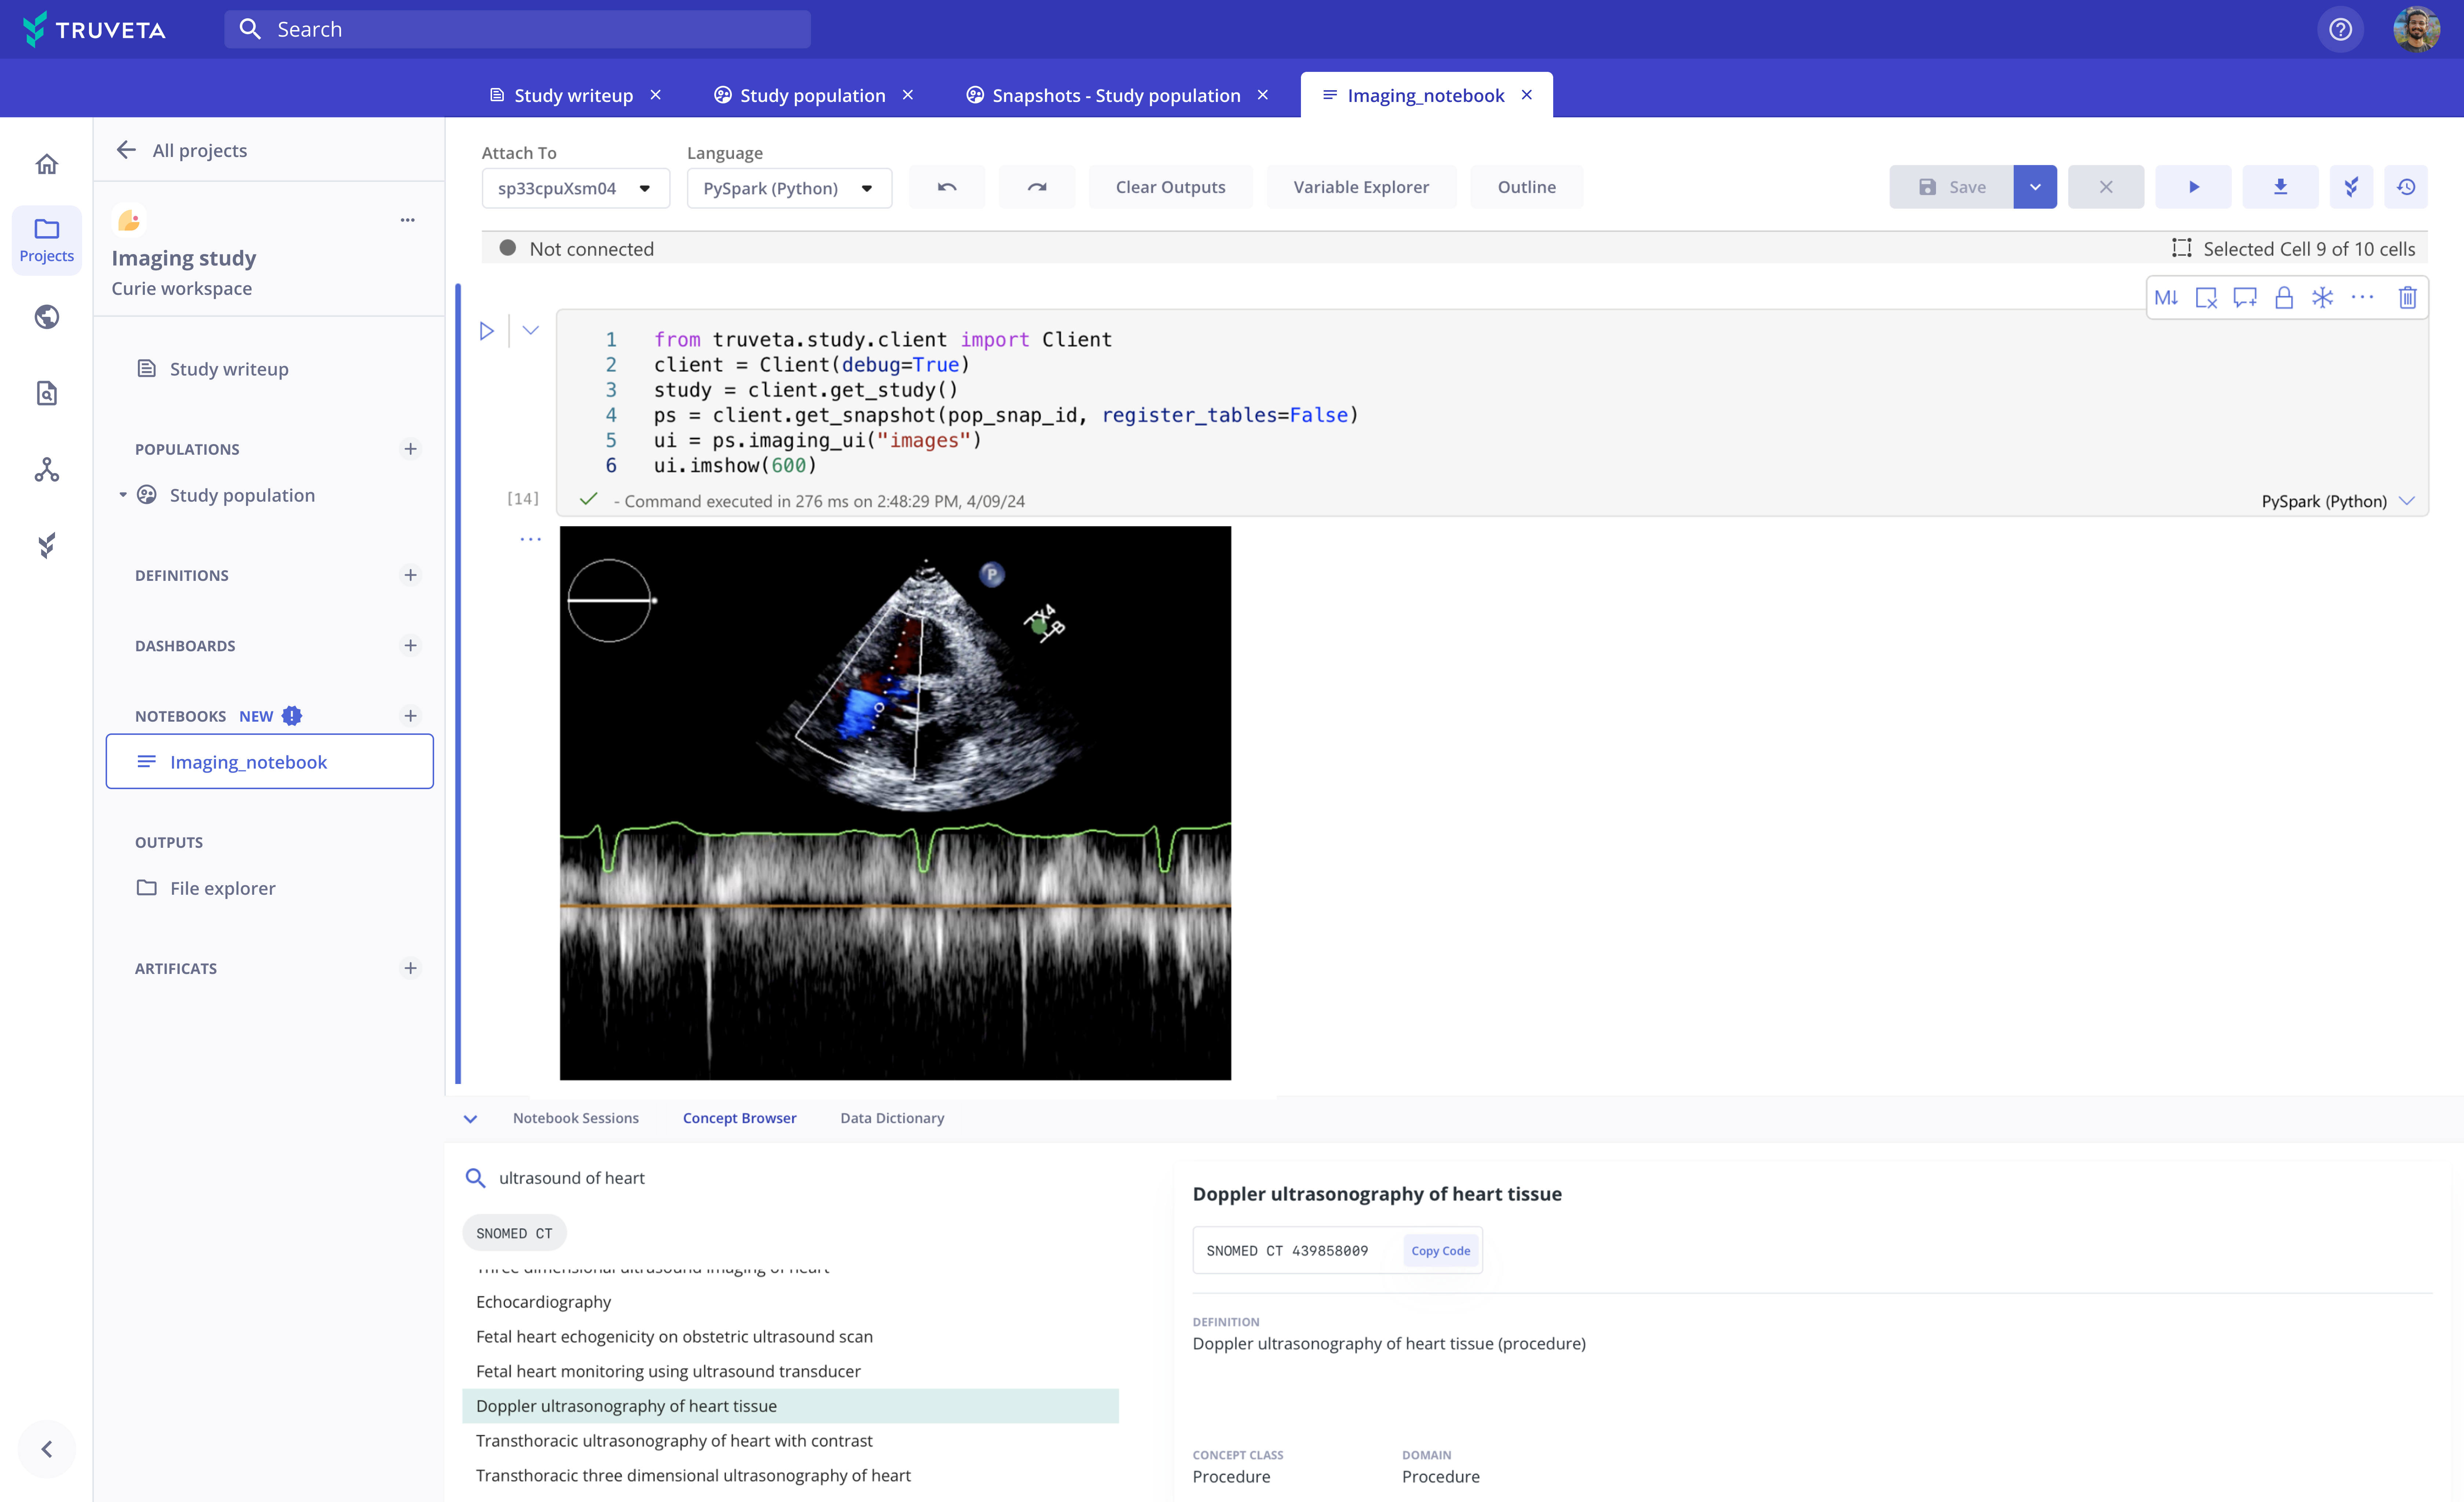

Truveta Studio enables researchers to preview images and easily annotate using built-in tools.

Research using echocardiography doppler for machine learning

De-identified images can be analyzed in notebooks in Truveta Studio and exported for studying imaging-based outcomes and observations, AI/machine learning model development, or inclusion in publications.